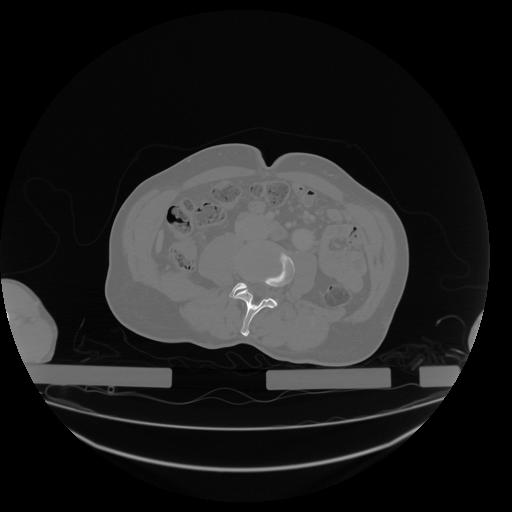

34 CUERPO,CE,Vol,1.0,CUERPO,,